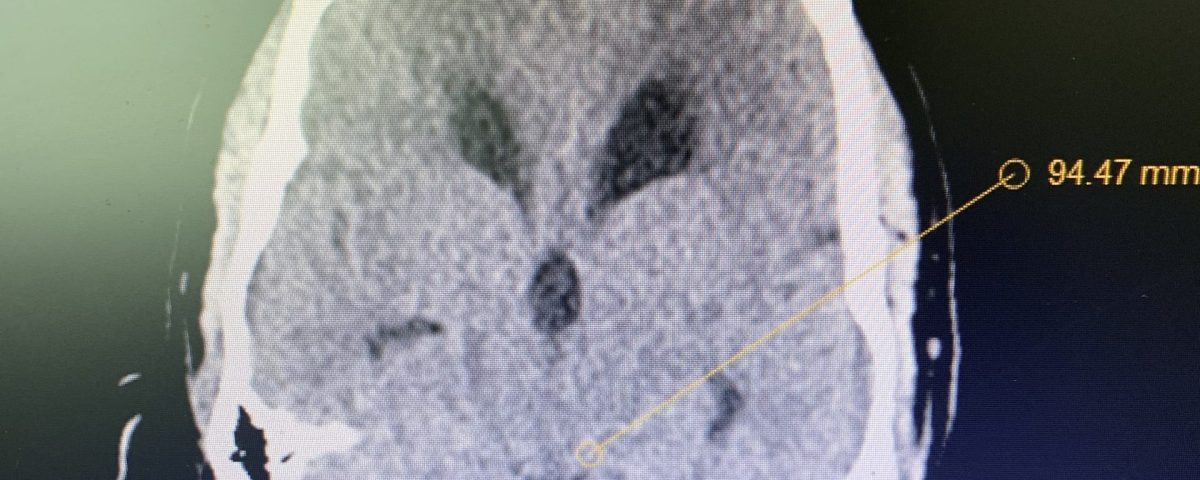

Figure 1A: Pre-operative MRI

Figure 1B,C: Pre-operative CT images.

Prior to shunting, a head CT was obtained and the head CT in addition to documenting a patten of obstructive hydrocephalus suggested a possible mass lesion compressing the aqueduct at its inferior aspect. Figure #1 demonstrates the hydrocephalus and the possible lesion. A decision was made at this point that the patient had obstructive hydrocephalus that was now symptomatic and he was taken for a laparoscopic-assisted ventriculoperitoneal shunt.